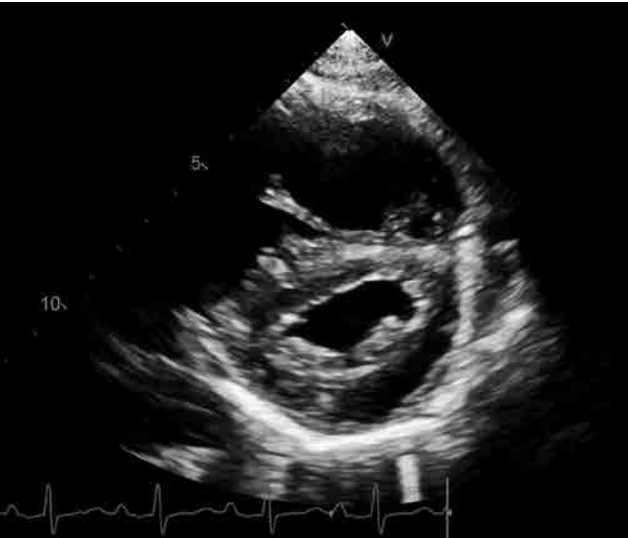

O achado exibido na imagem acima e sua correlação clínica são

retificação sistólica do septo interventricular; sobrecarga de pressão do ventrículo direito.

retificação diastólica do septo interventricular; sobrecarga de pressão do ventrículo direito.

retificação sistólica do septo interventricular; sobrecarga de volume do ventrículo direito.

retificação diastólica do septo interventricular; sobrecarga de volume do ventrículo direito.

retificação sistólica do septo interventricular; bloqueio de ramo direito.